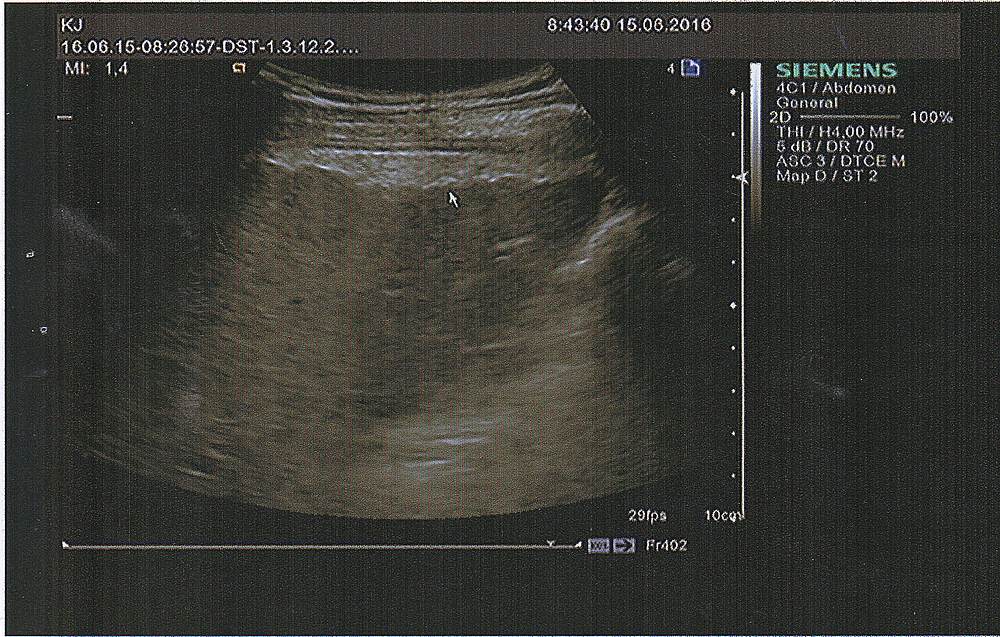

Всем -Привет ! Анализы фибротеста нифига не дали из-за невозможности составить график,низкий гаптоглобин. Мой областной гастроэнтеролог сказала ,что с Синево такое бывает .Посоветовала сделать эластографию. Сказала.что всё что там будет ,нас вполне устраивает без фибротеста,что б определить время курса Виропак Плюс / Viropack Plus (Египетский Харвони Harvoni) – новый препарат для лечения хронической формы гепатита С генотипа 1. Не требует комбинации с рибавирином и интерфероном. ....(Соф+Лед) Эти данные я Вам предоставляю,может кто ,что нибудь мне тоже по этим показателям поведает...Кто шарит,цирроз есть или таки ещё можно бросить вызов и сказать гепатиту нет ! ?